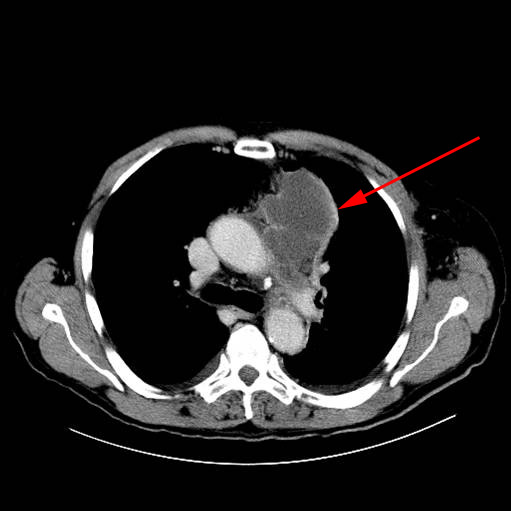

CT-skanning af thorax. Proces (pil) tæt på mediastinum med kantopladning efter indgift af kontrast. Biopsi viser primær lungecancer.